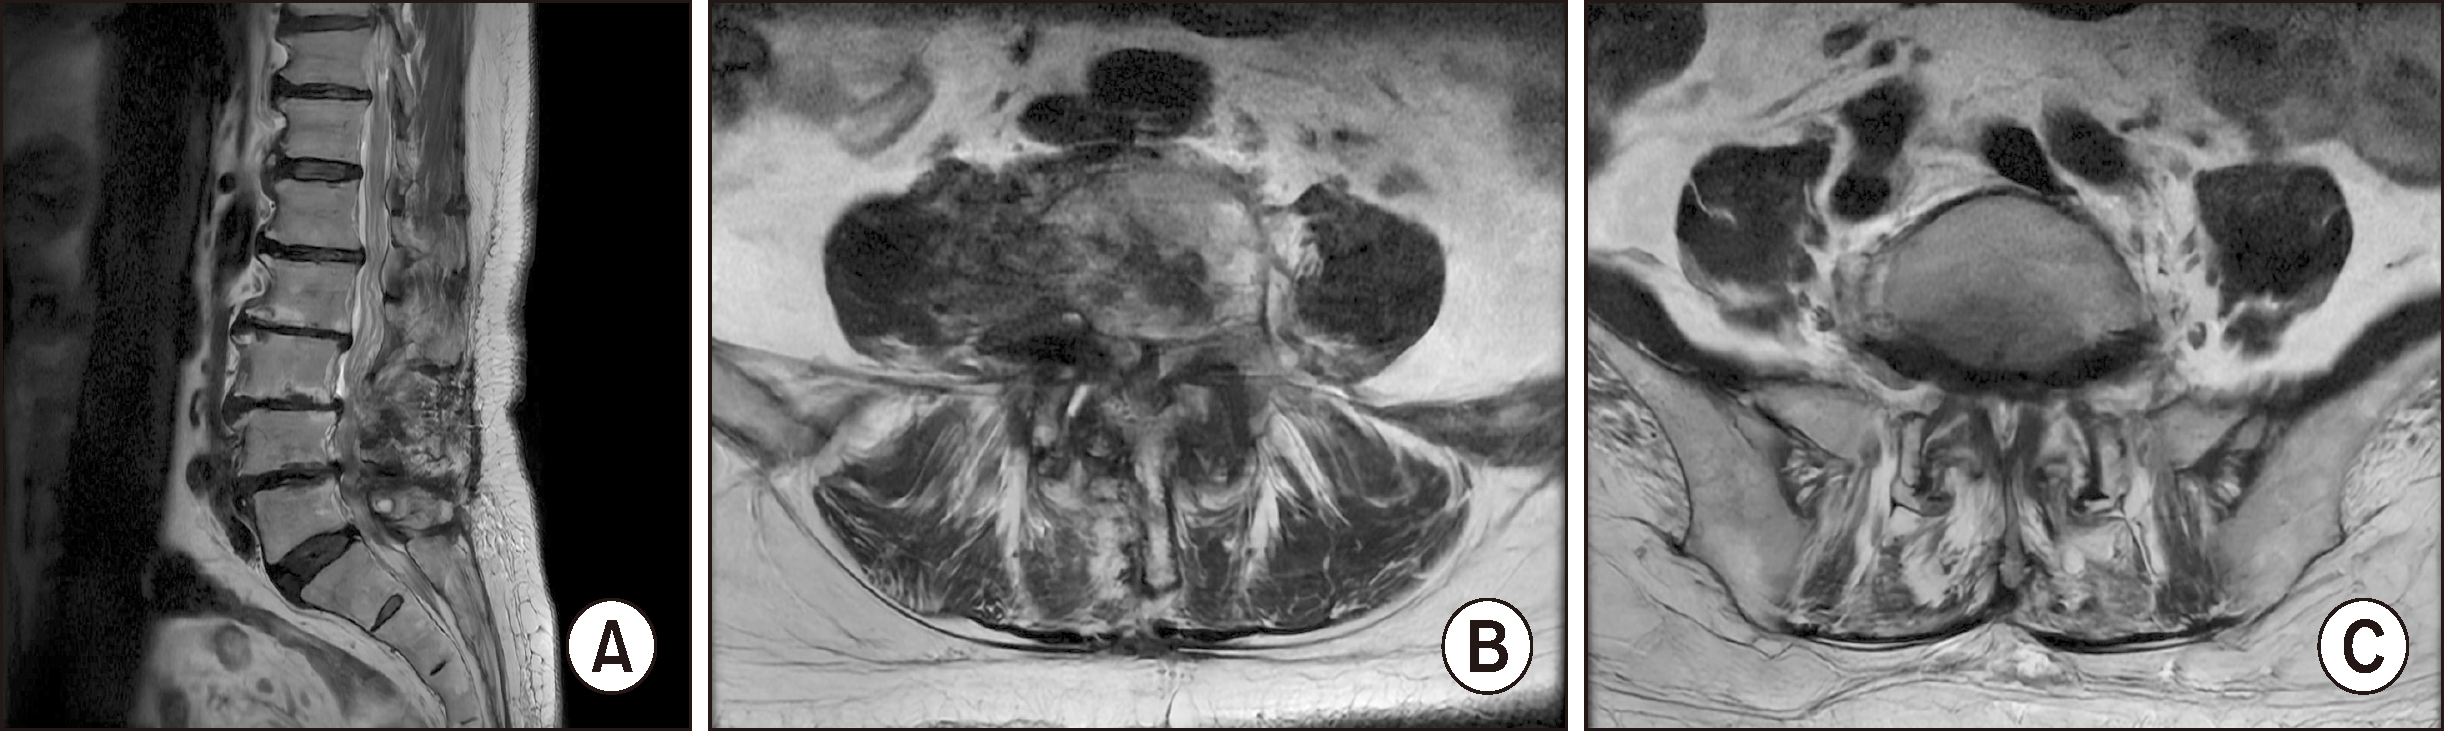

73세 여자가 1년 반 전부터 시작된 우측 후족부 궤양이 악화되어 내원하였다. 환자는 우측 후족부에 굳은살이 생겨서 자가 제거한 뒤 궤양이 발생하여 주기적으로 타원에서 드레싱 및 항생제 복용을 하였으나 호전이 없고 점진적으로 악화되었다고 한다. 그리고 본원에 내원하기 2주 전에 오한과 발열이 발생하여 타원에서 입원 치료를 하였으나 창상에 호전이 없고 골수염이 의심되어 본원으로 전원되었다. 고혈압 및 이상지질혈증의 과거력이 있었으며, 당뇨, 스테로이드 주사, 흡연, 류마토이드 관절염 등의 과거력은 없었고, body mass index는 27.6 kg/m2이었다. 4년 전 우측 하지의 근력 및 감각 저하 소견 보여 척추관 협착증으로 진단 후 요추 제 3, 4, 5번의 후궁절제술을 받았으나 우측 하지의 근력 및 감각 저하는 호전되지 않았다고 하며, 내원 1년 전부터 보행이 불가하였다고 한다. 허리 자기공명영상 검사에서 중등도 이상의 척추관 협착증(spinal stenosis) 및 추간공 협착증(foraminal stenosis)이 요추 제 4∼5번, 요추 제 5번∼천추 제 1번에서 확인되었다(Fig. 1A, B). 근전도(electromyography) 및 신경전도 검사(nerve conduction study)에서 요추 제 5번 및 천추 제 1번의 만성 요천추신경근병증(lumbosacral radiculopathy)이 확인되었다.

Figure 1

Sagittal T2-weighted magnetic resonance image of L-spine (A). Axial T2-weighted magnetic resonance image of L4-5 level (B) and L5-S1 level (C). The magnetic resonance images show severe central canal stenosis at the L4-5 level (B) and moderate neural foraminal stenosis at the L5-S1 level (C).